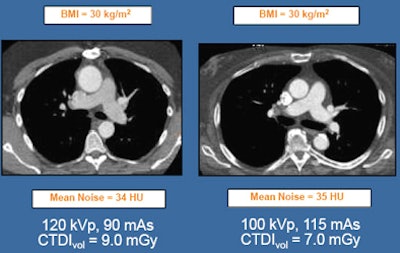

In the absence of real standards, kVp levels are usually based on visual assessment of patient size. Sometimes more objective measures such as patient weight and body mass index are used. Several studies, mostly from Europe, have suggested 100 kVp for patients weighing 85 kg or less. One group recommends 80 kVp for patients weighting 60 kg or less.

The studies represent a kind of standard that radiologists can look to in the absence of true guidelines, Halliburton said.

| Studies support the use of low-kVp cardiovascular imaging. All images courtesy of Sandra Halliburton, Ph.D. |